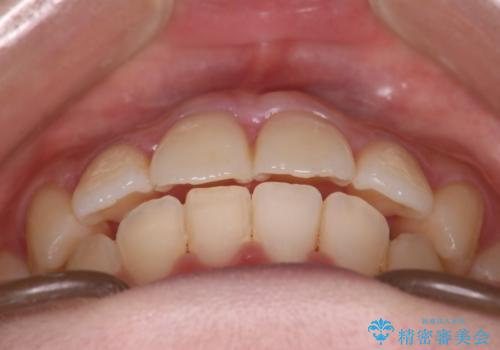

【インビザライン】マウスピースで開咬改善

- 開咬を主訴に来院されました。

IPR(歯と歯の間を削る処置)と顎間ゴムを行いながら、インビザラインで開咬を治療する計画を立てました。

治療をしながら、MFT(口腔筋機能療法)も行っていくことにしました。

歯の移動量が多いケースでしたが、患者様にマウスピースの使用とゴム掛けを頑張っていただいたので

リファイメント1回のみで治療を終わることができました。